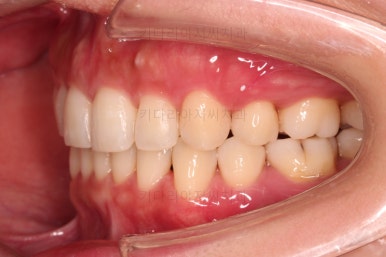

초진 시 입안의 모습인데요.

왜 그런지 비밀이 풀리는 것 같죠?

윗니는 한 쪽이 치아 2개가 결손이면서 유치가 하나 남아있고요.

아랫니는 한 쪽은 1개, 반대편은 2개 치아가 결손이었습니다.

도합 5개의 치아가 결손이었는데요.

결손 위치의 갯수가 위아래 좌우 다 달라서 중앙선이 맞을래야 맞을 수가 없는 상황이었죠.

결손치아 주위 치아들은 쓰러지고 비틀어져 있어서 장기적으로 좋지 못한 상황이었고요.

좀 더 디테일하게 윗니 작은 앞니 1개가 왜소치아라서 치아 크기도 맞지 않은 상황이었습니다.